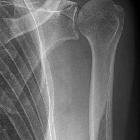

Bogige

Weichteilüberlagerung proximale Humerusschaft in Schulteraufnahme rechts

Weichteilüberlagerung proximaler Humerusschaft in Schulteraufnahme